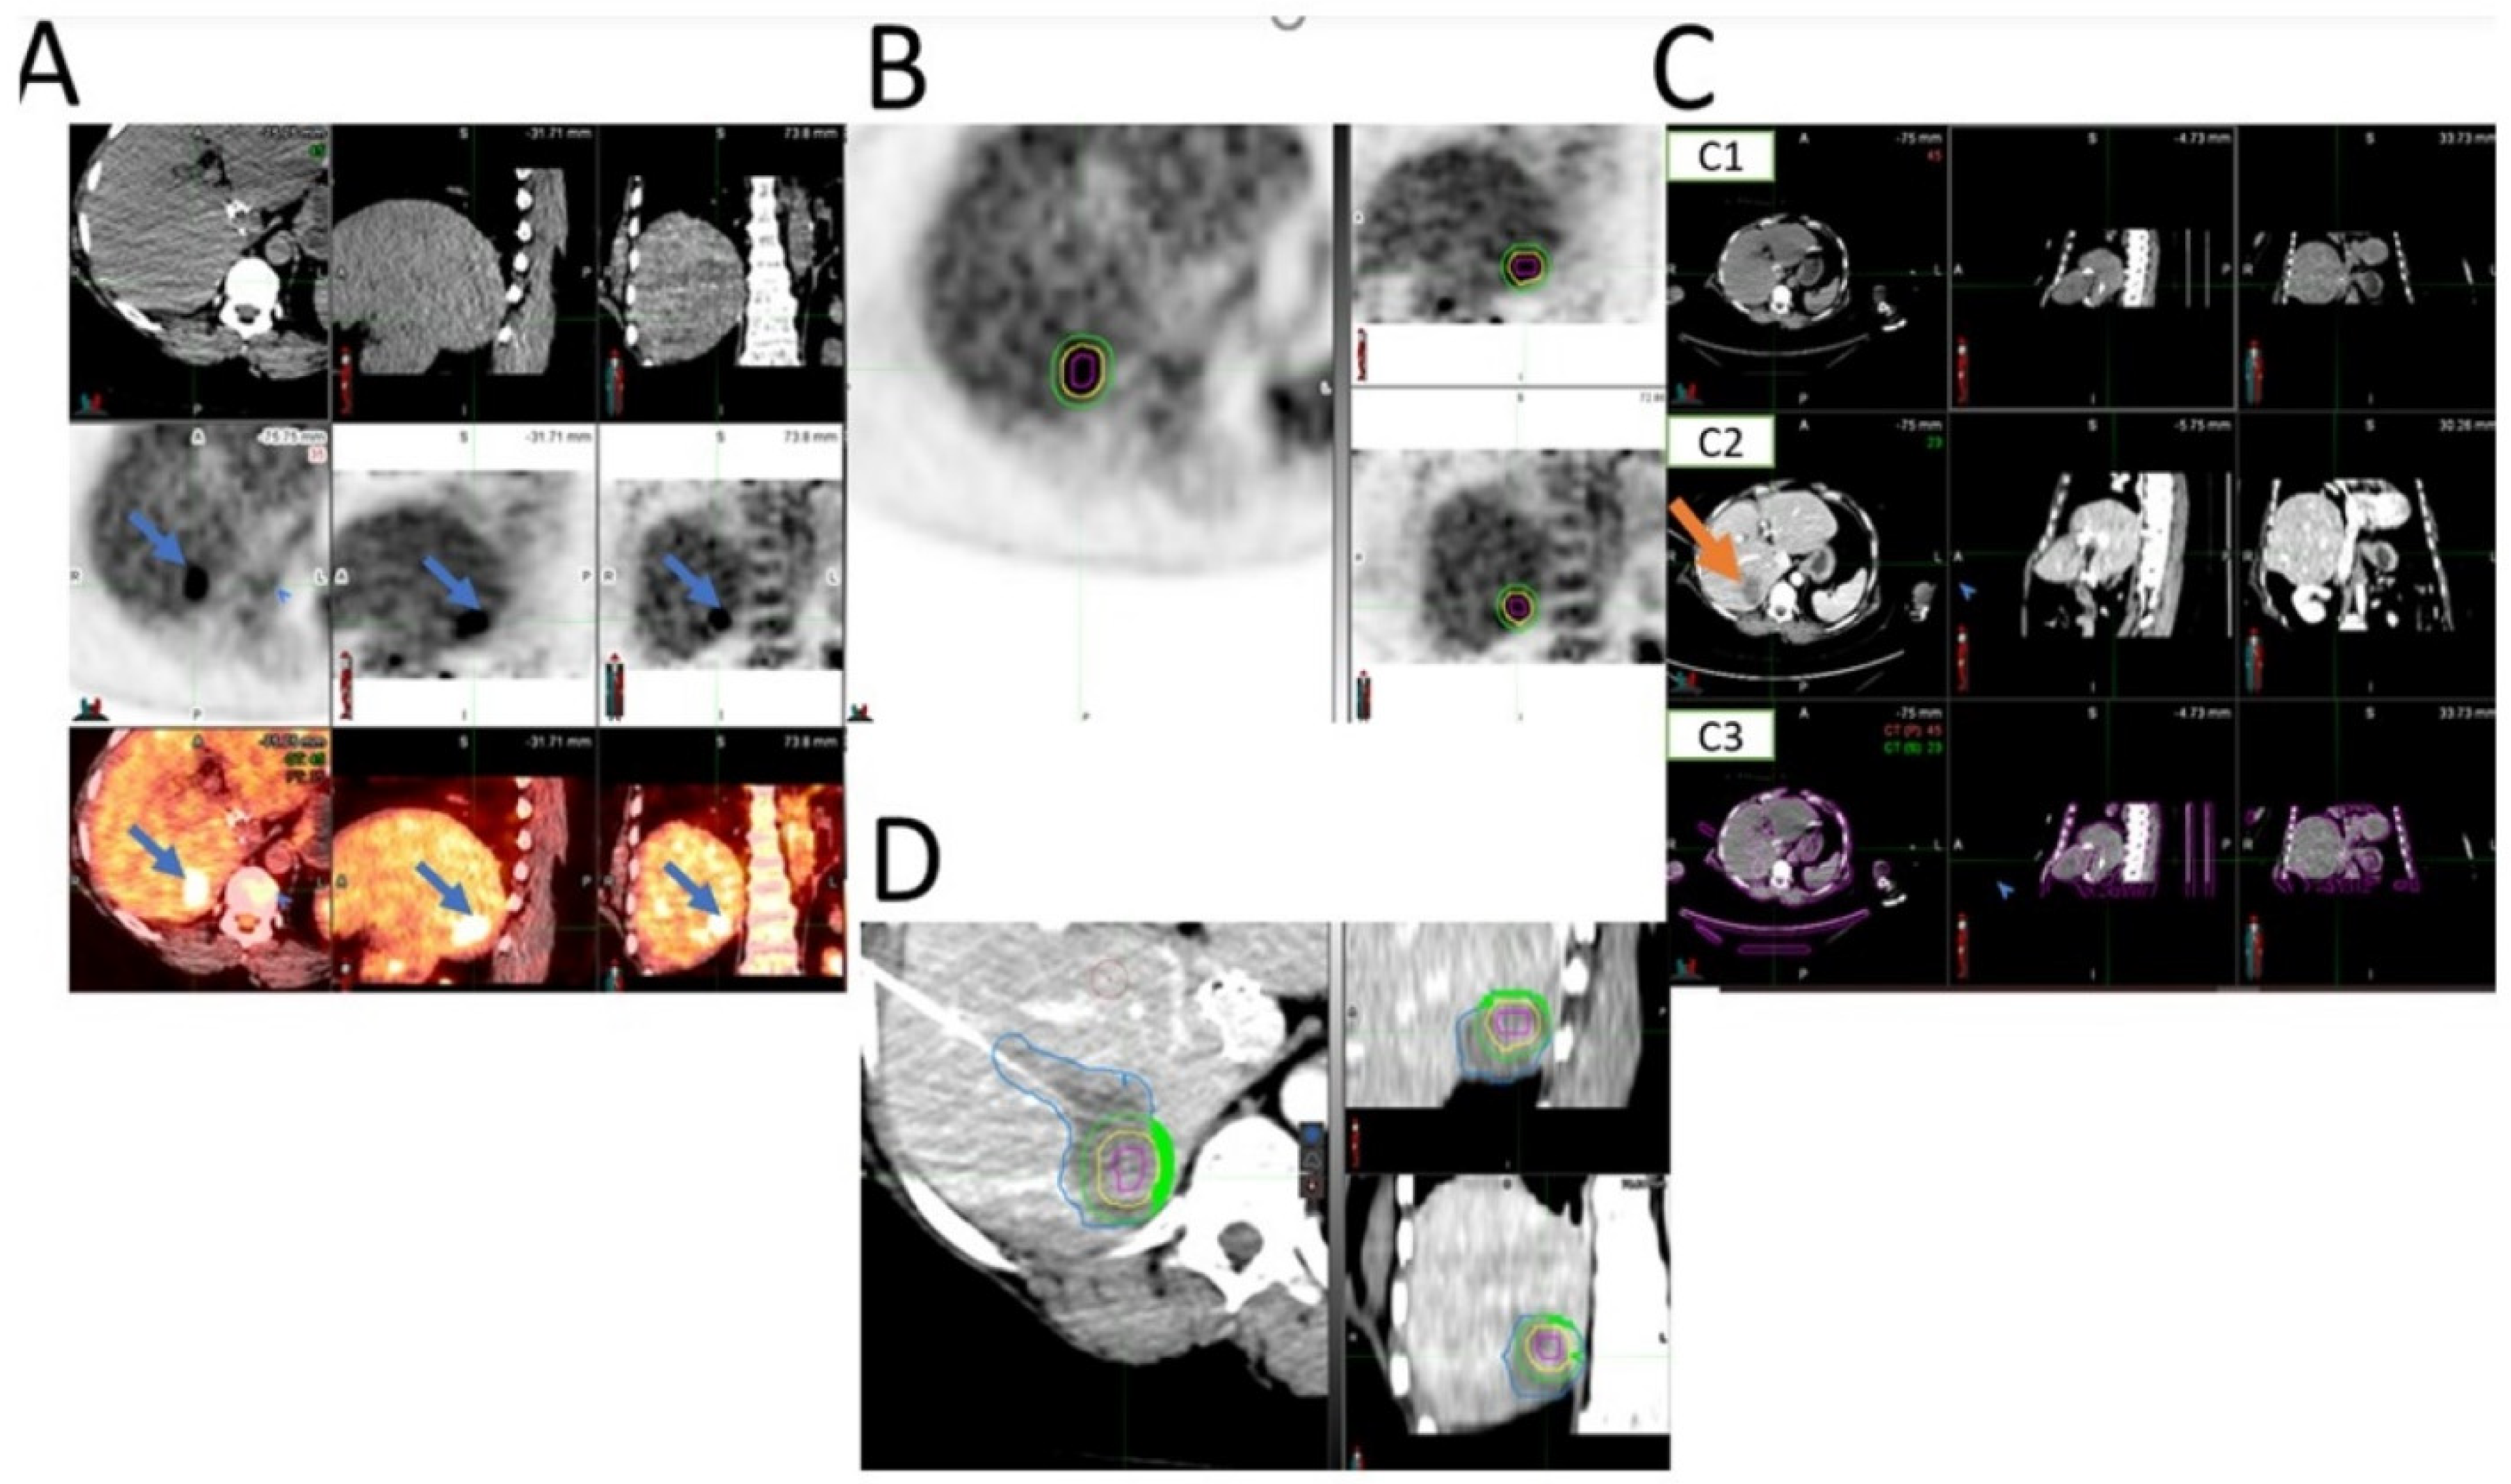

- Ryan, E.R.; Sofocleous, C.T.; Schöder, H.; Carrasquillo, J.A.; Nehmeh, S.; Larson, S.; Thornton, R.; Siegelbaum, R.H.; Erinjeri, J.P.; Solomon, S.B. Split-Dose Technique for FDG PET/CT–guided Percutaneous Ablation: A Method to Facilitate Lesion Targeting and to Provide Immediate Assessment of Treatment Effectiveness. Radiology 2013, 268, 288–295. [Google Scholar] [CrossRef]

- Cornelis, F.H.; Petre, E.N.; Vakiani, E.; Klimstra, D.; Durack, J.C.; Gonen, M.; Osborne, J.; Solomon, S.B.; Sofocleous, C.T. Immediate Postablation 18F-FDG Injection and Corresponding SUV Are Surrogate Biomarkers of Local Tumor Progression After Thermal Ablation of Colorectal Carcinoma Liver Metastases. J. Nucl. Med. 2018, 59, 1360–1365. [Google Scholar] [CrossRef] [PubMed]

- Cornelis, F.; Storchios, V.; Violari, E.; Sofocleous, C.T.; Schoder, H.; Durack, J.C.; Siegelbaum, R.H.; Maybody, M.; Humm, J.; Solomon, S.B. 18F-FDG PET/CT is an Immediate Imaging Biomarker of Treatment Success after Liver Metastasis Ablation. J. Nucl. Med. 2016, 57, 1052–1057. [Google Scholar] [CrossRef] [PubMed]

- Casadaban, L.C.; Catalano, P.J.; Lee, L.K.; Hyun, H.; Tuncali, K.; Gerbaudo, V.H.; Shyn, P.B. Assessing ablation margins of FDG-avid liver tumors during PET/CT-guided thermal ablation procedures: A retrospective study. Eur. J. Nucl. Med. 2021, 48, 2914–2924. [Google Scholar] [CrossRef] [PubMed]